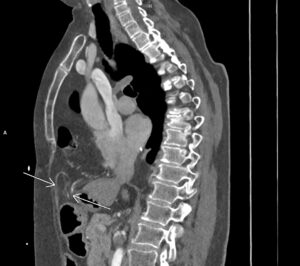

Figurile 1 şi 2: sagital CT în timp venos torace şi abdomen superior

Discuţie caz nr 127: se evidențiază hernierea intratoracică a jumătății distale a colonului ascendent, unghiului hepatic al colonului și a unei părți din colonul transvers printr-un orificiu herniar situat anterior de partea dreapta împreună cu o parte din mezocolon.

DE LUAT ACASĂ!!! Hernia Morgagni este una dintre herniile diafragmatice congenitale și este caracterizata de hernierea prin foramenul Morgagni. În comparație cu herniile Bochdalek, herniile Morgagni tind să fie: localizate anterior, mai des pe partea dreaptă ( aproximativ 90%), mici, rare aproximativ 2% din herniile diafragmatice congenitale), cu risc scăzut de prolaps.